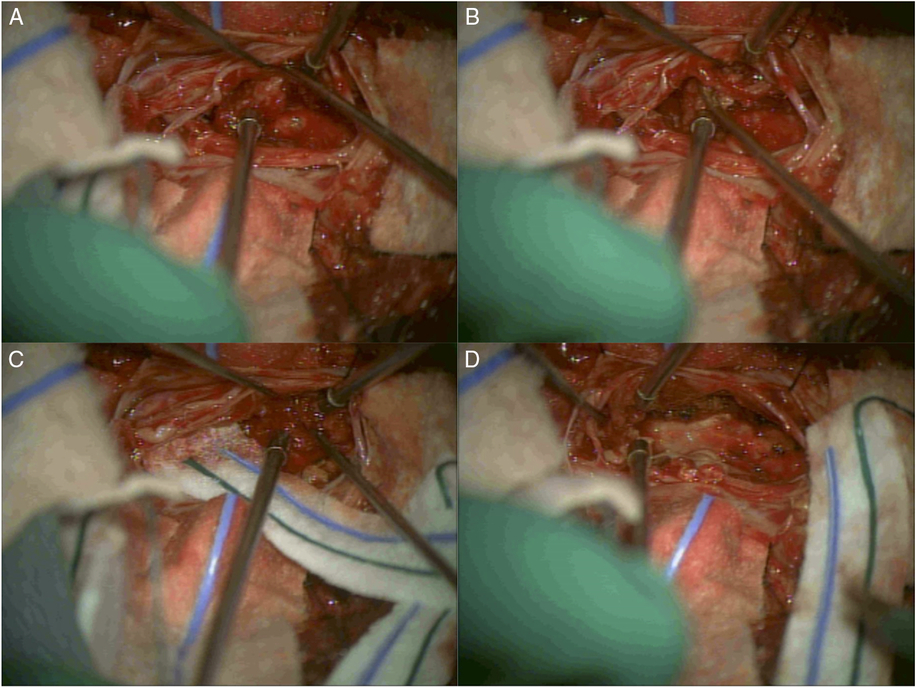

Intraoperatively, the cerebrospinal fluid appeared xanthochromic, and the lesion was intimately associated with the cauda equina nerve roots. For this reason, gross total resection was not attempted. Great care was taken while debulking the tumor to spare the nerve roots, and a radical resection with good decompression of the cauda equina was achieved (Figure 2). A watertight dural repair was performed and tested under Valsalva maneuver before closure of the fascia and skin.

Figure 2: Intraoperative images of surgical resection of the L5-S1 intradural tumor. (A) After durotomy was performed at the level of L5-S1, a tumor was visualized and found to be intimately associated with the nerve roots in the cauda equina. (B) Careful dissection, identifying the nerve roots of the cauda equina and separating them from the tumor mass. (C) Radical resection of the tumor took place while great care was taken to protect and spare the nerve roots. (D) Completion of the resection and good decompression of the cauda equina was achieved.